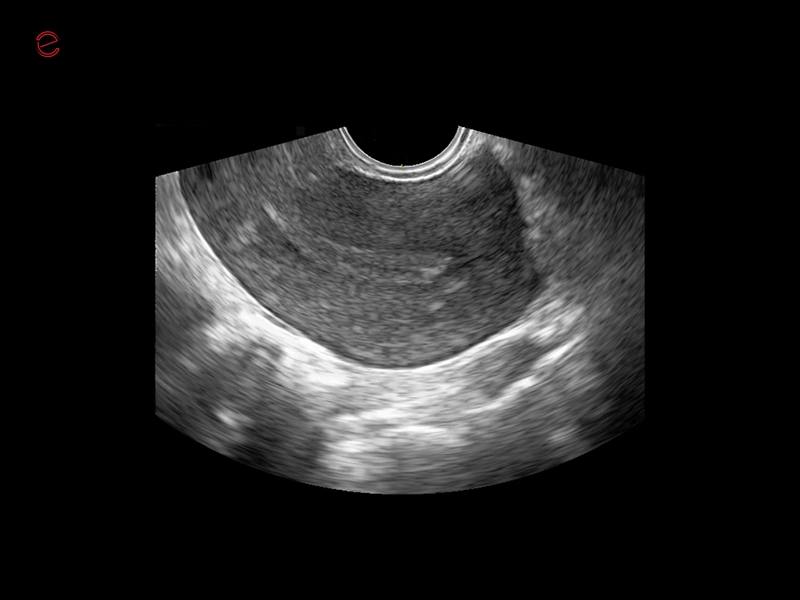

Q7 - Endo

Q7 - Endo

MyLab™X1 Go - WH Endometrium

MyLab™X1 Go - WH Endometrium

MyLab™X1 Go - Gyn

MyLab™X1 Go - Gyn